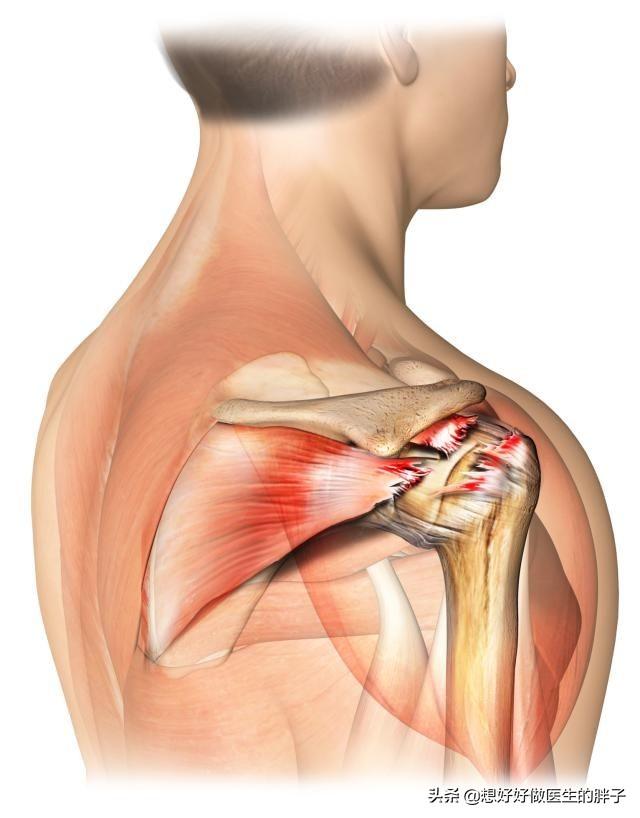

よく痛む部位や影響を受ける筋肉は、三角筋、小胸筋、棘下筋、棘上筋、外側広筋、広背筋、上腕二頭筋、回旋筋腱板の滑液包である。ツボは主に骨と腱の付着部にある。或これらの筋肉を支配する神経の敏感な箇所を触診すると、筋状に硬くなっているのが感じられる。

要約すると、これらの筋肉群はすべて、以下の筋肉群の一部である。C5-8およびT1-2神経根支配放散痛の範囲も、これらの神経の前枝の支配範囲に対応している。したがって五十肩は頚椎症の特殊なタイプでもある。。

肩のインピンジメント症候群についてお話ししたときに、ローテーターカフについて少し触れました。腱板はローテーター・カフとも呼ばれる。肩関節の動きにおいて非常に重要な役割を担っている。主に4つの腱から構成され、肩関節の上部にある。手の4本の指が肩関節の上腕骨頭をつかむように、上腕骨頭はあらゆる方向に動くことができる。。